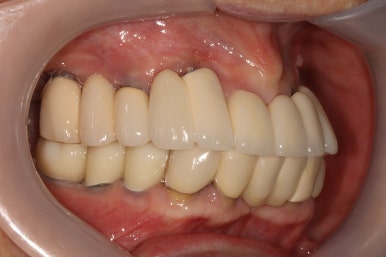

생각보다 임시치아보다 훨씬 매끈한 표면과 비슷한 색깔을 자랑하는 지르코니아 크라운입니다.

아마 어금니에 임플란트가 생긴건가? 싶으실거에요.

오스템 원가이드 네비게이션 임플란트 시스템을 이용하면, 정교하게 이상적인 위치에 임플란트를 심어낼 수 있어 자연스러운 임플란트 보철물을 제작하는데 많은 도움을 받을 수 있습니다!!

최종 완성된 보철물은 상당히 이상적인 형태를 갖고 있습니다.

이제 드디어 부분틀니를 쓰지 않아도 되는 ... 행복한 순간입니다.

차이를 별로 못느끼실 수 있겠지만, 임플란트 보철물 완성 6개월 후 방문 때 구강내 사진입니다.

감사히도 환자분께서 상당히 깨끗하게 유지하고 계셔서, 잇몸에 염증하나 없이 너~무 보기 좋더라구요.

어금니 좌측

어금니 우측

좌우측 측면 사진 비교시, 아래 어금니 임플란트로 깔끔하게 메꿔진 빈 공간이 인상적입니다!